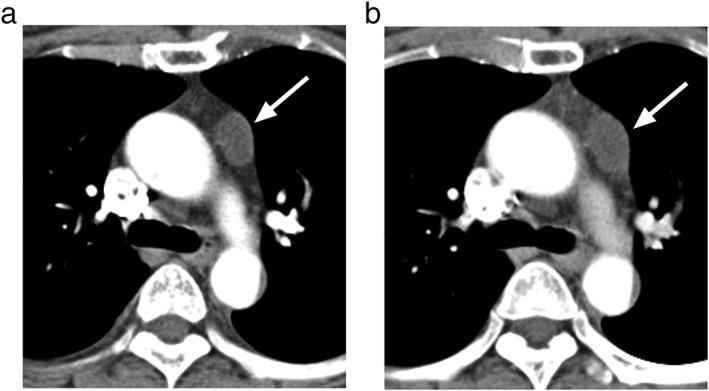

The growth rate of thymic epithelial tumors (TETs) and thymic cysts was investigated to determine whether they can be differentiated and clinico-radiological predictors of interval growth was identified.

This retrospective study included 122 patients with pathologically proven thymic cysts (n = 56) or TETs (n = 66) who underwent two serial chest computed tomography scans at least eight weeks apart. Average diameters and attenuation were measured, volume-doubling times (VDTs) were calculated, and clinical characteristics were recorded. VDTs were compared using the log-rank test. Predictors of growth were analyzed using the log-rank test and Cox regression analysis.

The frequency of growth did not differ significantly between TETs and thymic cysts (P = 0.279). The VDT of thymic cysts (median 324 days) was not significantly different from that of the TETs (median 475 days; P = 0.808). Water attenuation (≤ 20 Hounsfield units) predicted growth in thymic cysts (P = 0.016; hazard ratio 13.2, 95% confidence interval 1.6-107.3), while lesion size (> 17.2 mm) predicted growth in TETs (P = 0.008 for size, P = 0.029 for size*time). For the growing lesions, the positive and negative predictive values of water attenuation for thymic cysts were 93% and 80%, respectively.

The frequencies of interval growth and VDTs were indistinguishable between TETs and thymic cysts. Water attenuation and lesion size predicted growth in thymic cysts and TETs, respectively. Among the growing lesions, water attenuation was a differential feature of thymic cysts.